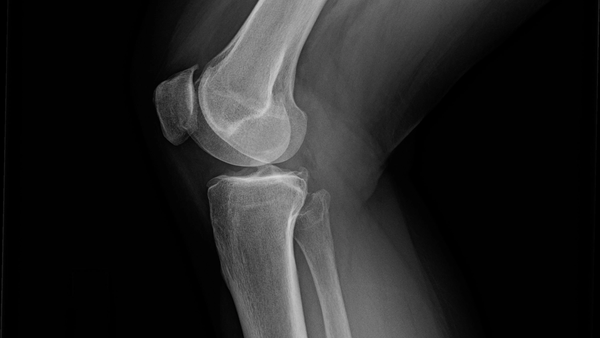

Kneartrose

Kneartrose påvirker leddstrukturen i kneet og utvikler seg gradvis over lang tid. Risikofaktorer inkluderer alder, arvelighe faktorer, overvekt, tidligere skader og uvanlig store belastninger. Kneartrose er en av de mest utbredte muskel- og skjelettplagene som fører til redusert livskvalitet og uførhet.